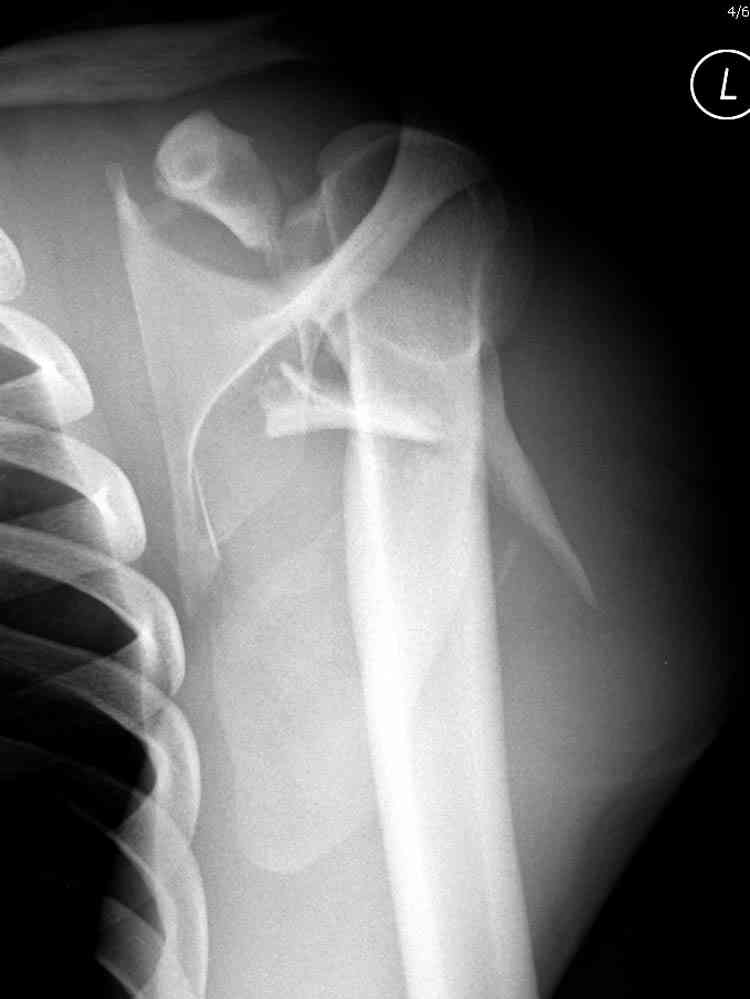

дравствуйте, коллеги. Мужчина 24 лет. Сегодня был прооперирован по Сушко-Илизарову (давно порывался, наконец-то руки дошли :)) На снимке перелом угла лопатки. Довольно крупный размер осколка. Следует ли оперировать такой перелом?Если есть резон оперативного лечения, то каким образом? (рекон. пластина, закрыто пришпилить спицами, винтами). ЭОПа в наличии нет. В области лопатки массивный отек мягких тканей. С уважением, Заднепровский Никита Николаевич

А где там сломанный угол лопатки? Стрелочкой покажите pls?

Для решения насчет оперативного вмещательства на лопатке сперва надо определиться с обьязательными ренгенологическими исследованиями, не менее трех стандартных проекций: прямая, аксиллярная и в позиции виде “Y”.

Прямую снимают под углом в 35 градусов от центра и вид “Y” в 90 градусов к нему. Несмотря на неудобства, больному необходимо сделать

аксиллярный снимок.

К-томографические и Трехмерные(3D)снимки крайне важны для определения внутрисуставных переломов и классификации.

Кроме анатомической классификации, переломы лопатки делятся на стабильные и нестабильные, внутри- и внесуставные и с вовлечением суставной поверхности.

Нестабильные внесуставные переломы лопатки типично сочетаются с переломами ключицы и ребер.